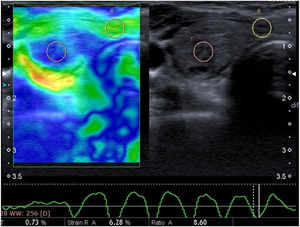

A routine B-mode ultrasound evaluation was obtained by having patients positioned on their backs with their necks slightly extended. B-mode ultrasonographic nodule features, such as size and side location (e.g., right, left), were recorded. SE was performed with a conventional ultrasound probe during a single US examination session using software connected to the machine. The probe was positioned perpendicular to the skin when pressure was applied, and lateral movement was avoided. The great cervical vessels were also avoided as much as possible. Additionally, strong initial compression was avoided due to the possibility of increasing the probability of false negative results. Patients were asked to hold their breath and not swallow during the examination in order to minimize the movement of the thyroid gland. After approximately seven to eight compression–relaxation cycles, the elastographic examinations were finalized. SR value measurements were obtained from appropriate relaxation waves on the velocity profile, and the SR was automatically calculated by the software. Each nodule was assessed based on different static images at least three times, with the mean value recorded as the final result. The radiologist performed the examination and evaluation for approximately 5–7 min for each patient. For the SR, the radiologist selected the rounded Region-Of-Interest (ROI), including the thyroid nodule and surrounding normal thyroid tissue or the ipsolateral Sternocleidomastoid Muscle (SCM), as a reference in order to provide a semi-quantitative analysis. The elastography score was also measured via the same method and determined by a color scale, ranging from green (i.e., softest components) to blue (i.e., hardest components). According to this assessment system, softer lesions are assigned lower elastography scores, while stiffer lesions are assigned higher elastography scores. The gray-scale images on the right and images of the strain elastogram on the left were displayed on the same screen for both methods (Figs. 1‒2).

Elastography score was based on a four-point scale according to the classification proposed by Asteria et al. (Fig. 3).14

Elasticity Score (ES) of thyroid nodules and its corresponding elastographic pattern proposed be Asteria et al.14